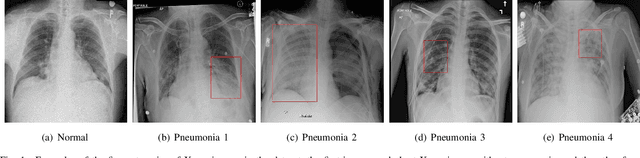

Abstract:Computer-aided X-ray pneumonia lesion recognition is important for accurate diagnosis of pneumonia. With the emergence of deep learning, the identification accuracy of pneumonia has been greatly improved, but there are still some challenges due to the fuzzy appearance of chest X-rays. In this paper, we propose a deep learning framework named Attention-Based Contrastive Learning for Class-Imbalanced X-Ray Pneumonia Lesion Recognition (denoted as Deep Pneumonia). We adopt self-supervised contrastive learning strategy to pre-train the model without using extra pneumonia data for fully mining the limited available dataset. In order to leverage the location information of the lesion area that the doctor has painstakingly marked, we propose mask-guided hard attention strategy and feature learning with contrastive regulation strategy which are applied on the attention map and the extracted features respectively to guide the model to focus more attention on the lesion area where contains more discriminative features for improving the recognition performance. In addition, we adopt Class-Balanced Loss instead of traditional Cross-Entropy as the loss function of classification to tackle the problem of serious class imbalance between different classes of pneumonia in the dataset. The experimental results show that our proposed framework can be used as a reliable computer-aided pneumonia diagnosis system to assist doctors to better diagnose pneumonia cases accurately.